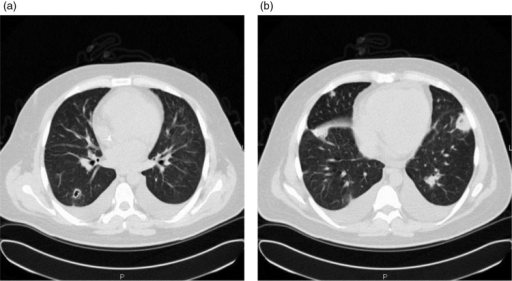

Isolated pulmonary valve endocarditis masquerading as community-acquired pneumonia Journal of Community Hospital Internal Medicine Perspectives